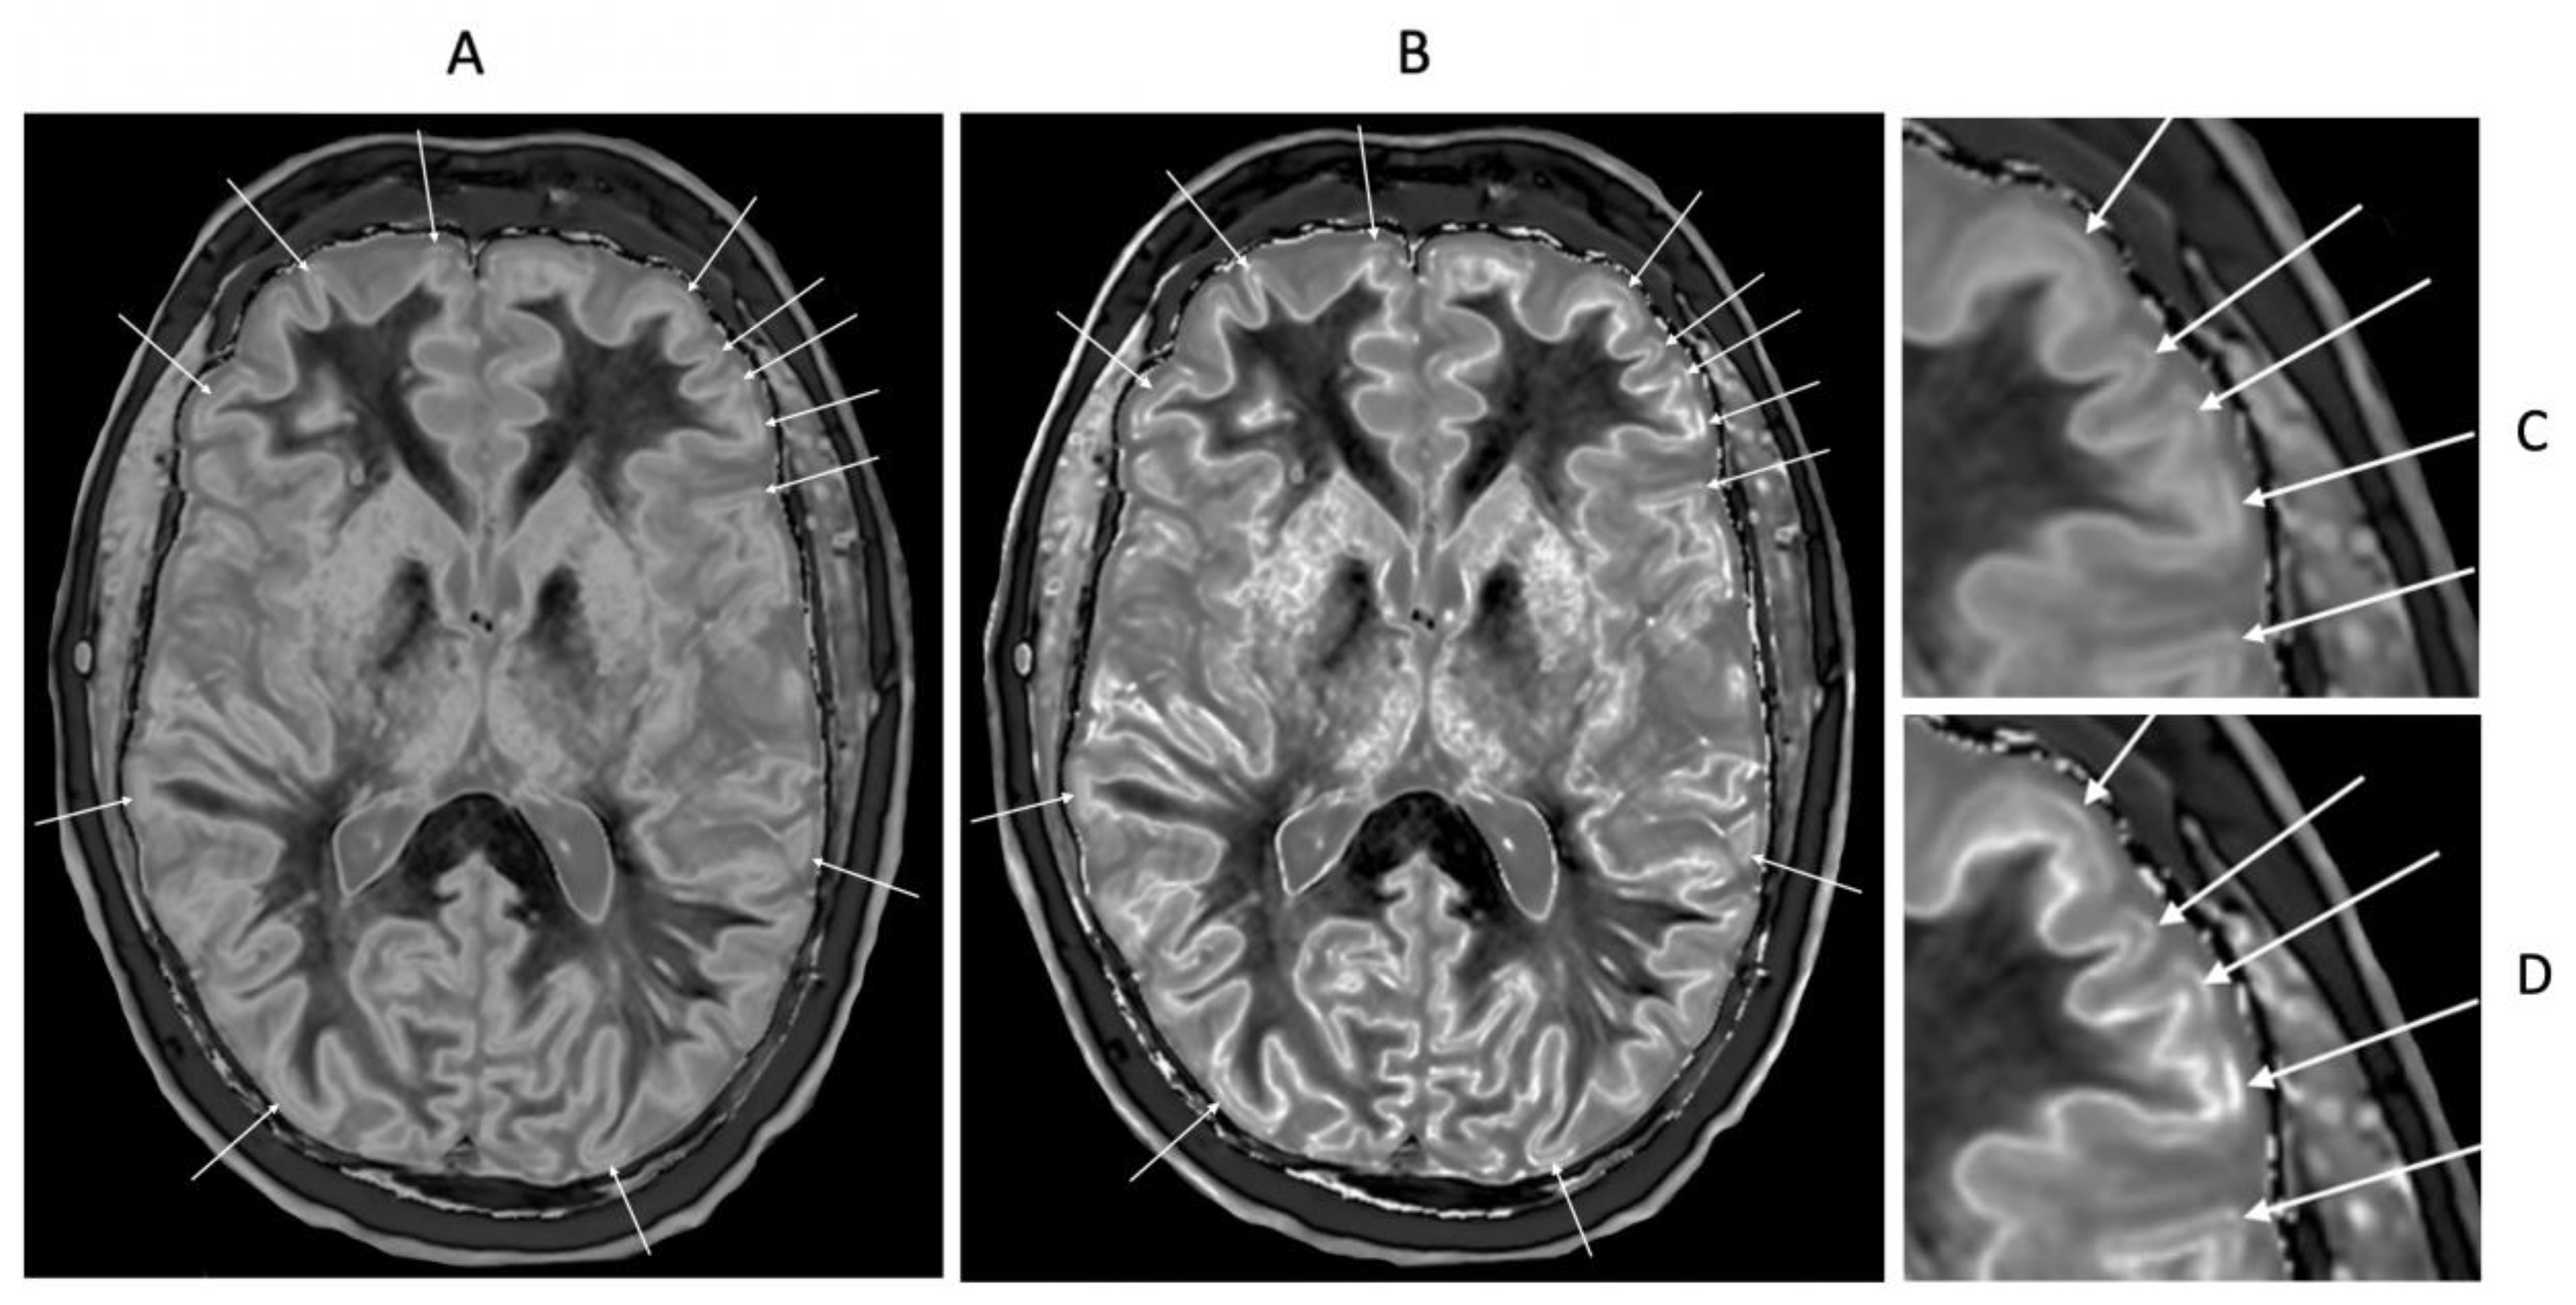

Figure 22.

46-year-old normal control. Narrow mD dSIR (A) and narrow mD lSIR (B) T1-BLAIR images with insets of anterior left cortex dSIR in (C) and anterior left cortex lSIR in (D). The boundaries between white matter and gray matter are seen with higher contrast and the contrast is seen with higher spatial resolution in (B) and (D) compared with (A) and (C). Bilaminar cortex signs are also seen with higher contrast and spatial resolution in (B) and (D) (white arrows). There are also small bubble signs in the putamen and medial thalamus which are better seen on the lSIR image (B) compared with the dSIR image (A).